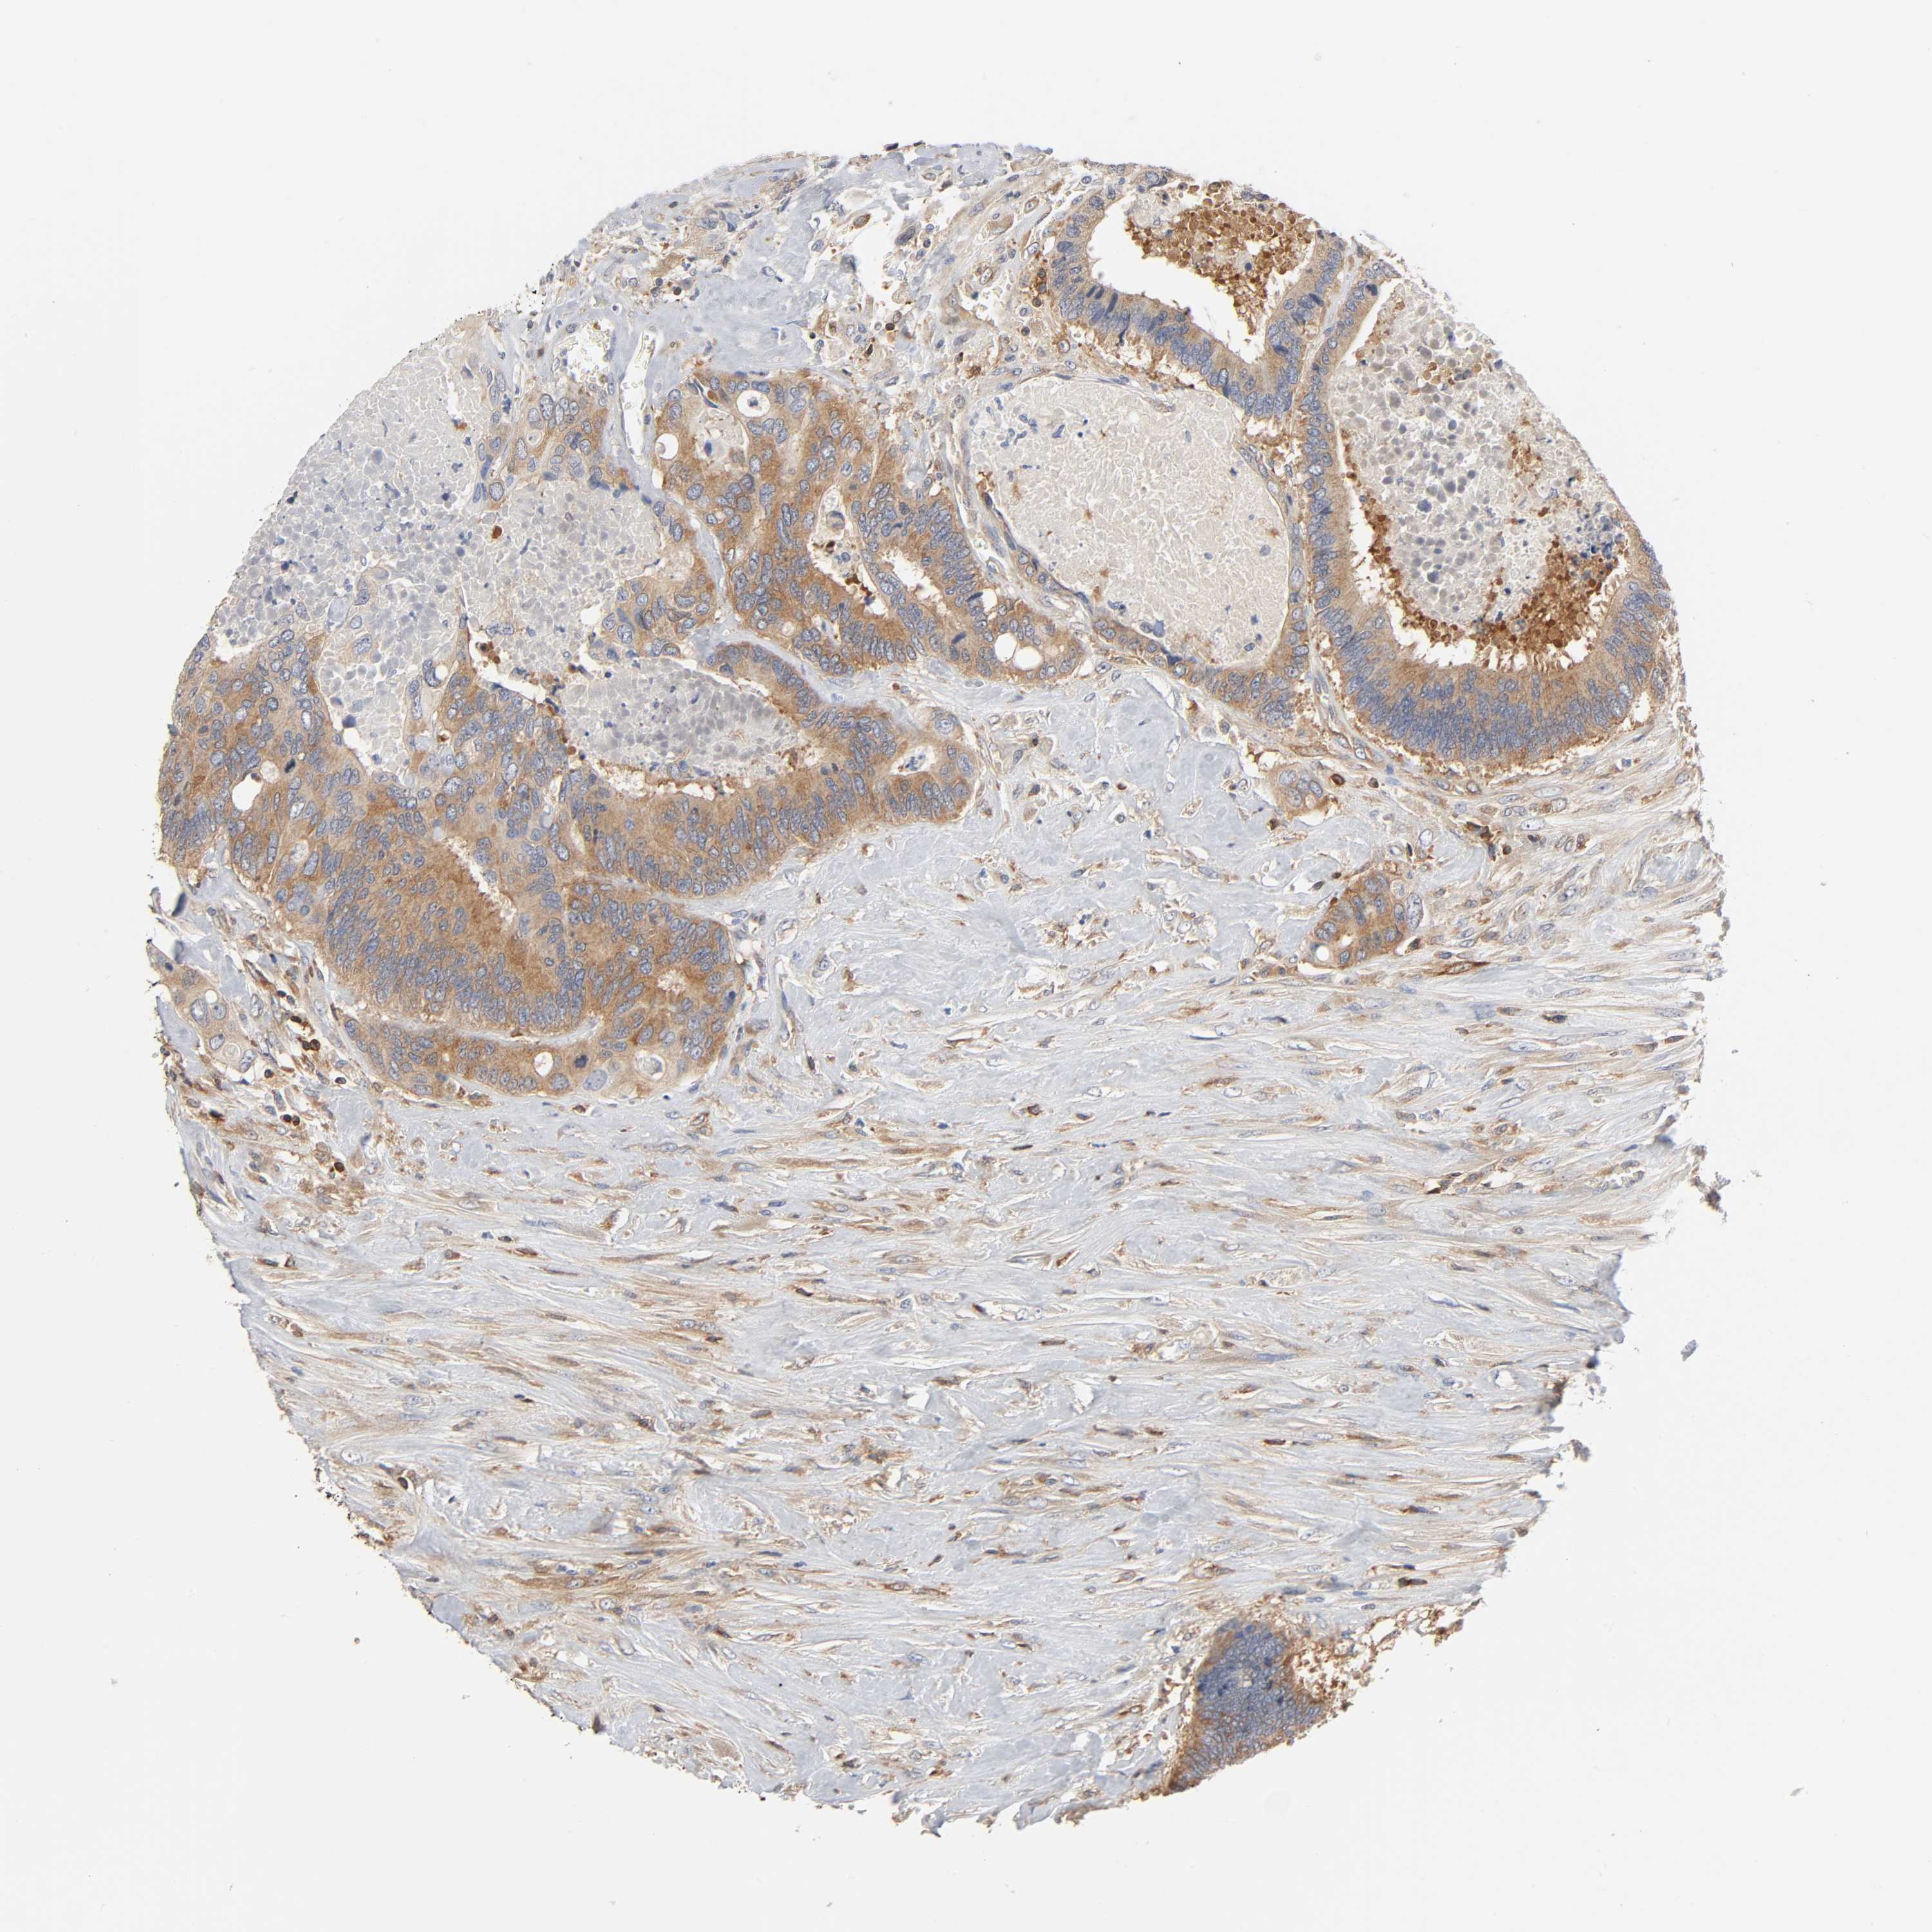

CANCER COLORECTAL CANCER Show tissue menu

COAD TCGA COAD VALIDATION READ TCGA READ VALIDATION PROTEIN COAD CPTAC PROTEIN EXPRESSION

ANTIBODIES

AND

VALIDATION